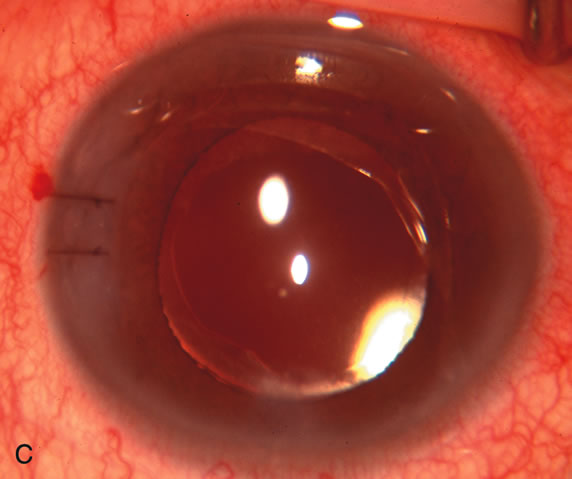

CATARACT EXTRACTION ALONE REDUCES IOP IN MOST EYES WITH ANGLE-CLOSURE GLAUCOMA

Uncomplicated cataract extraction substantially reduces IOP, along with the number of postoperative glaucoma medications in eyes with angle-closure glaucoma.146,147 When preoperative gonioscopy reveals PAS, along with adjacent areas of appositional closure, lens extraction alone in select cases may be a reasonable alternative to filtration surgery.148,149 Phacomorphic angle-closure disease due to enlargement of the lens with progressive angle crowding is eliminated following lens extraction. The width and depth of the anterior chamber angle in eyes with angle-closure glaucoma increases significantly after cataract extraction with IOL implantation and becomes similar to open-angle glaucoma and normal eyes.150,151 (Fig. 5). Combining phacoemulsification, IOL implantation, and limited goniosynechialysis is effective in the treatment of cataract and chronic angle-closure glaucoma.152 Phacoemulsification with implantation of a foldable IOL is more effective in reducing IOP and improving visual acuity than surgical peripheral iridectomy in eyes with acute angle-closure glaucoma.153

Fig. 5. Anterior chamber angle changes associated with lens extraction and PCIOL This 65-year-old Vietnamese woman has a long-standing history of chronic angle-closure glaucoma treated with laser peripheral iridectomy. The optic nerve demonstrated mild glaucomatous damage and IOP was moderately controlled on two antiglaucoma medications. The cataract was removed through temporal clear corneal phacoemulsification with foldable acrylic IOL. A. Symptomatic cataract in narrow-angle glaucoma eye with patent iridectomy. B. Intraoperative goniophotograph showing crowding of angle with increasing narrowness due to phacomorphic component. C. Intraoperative photograph showing temporal clear corneal approach with IOL in the capsular bag. D. Intraoperative goniophotograph demonstrating deepening of chamber angle following lens extraction. Proposed theories for IOP reduction following lens extraction with complete wound closure: